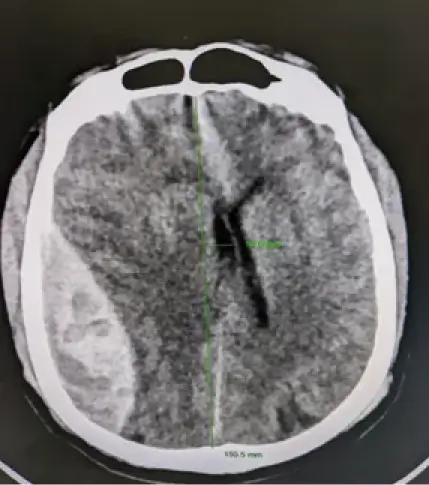

CT scan showed a huge extradural clot (150ml). Emergency craniotomy was performed within 20 minutes. Clot was extracted and bleeding was controlled. He gained consciousness and responded to verbal commands. His GCS improved and discharged home. However, he needs rehabilitation for at least 6 months to gain muscle strength, walking capability, regained bladder control.

EDH After Craniotomy